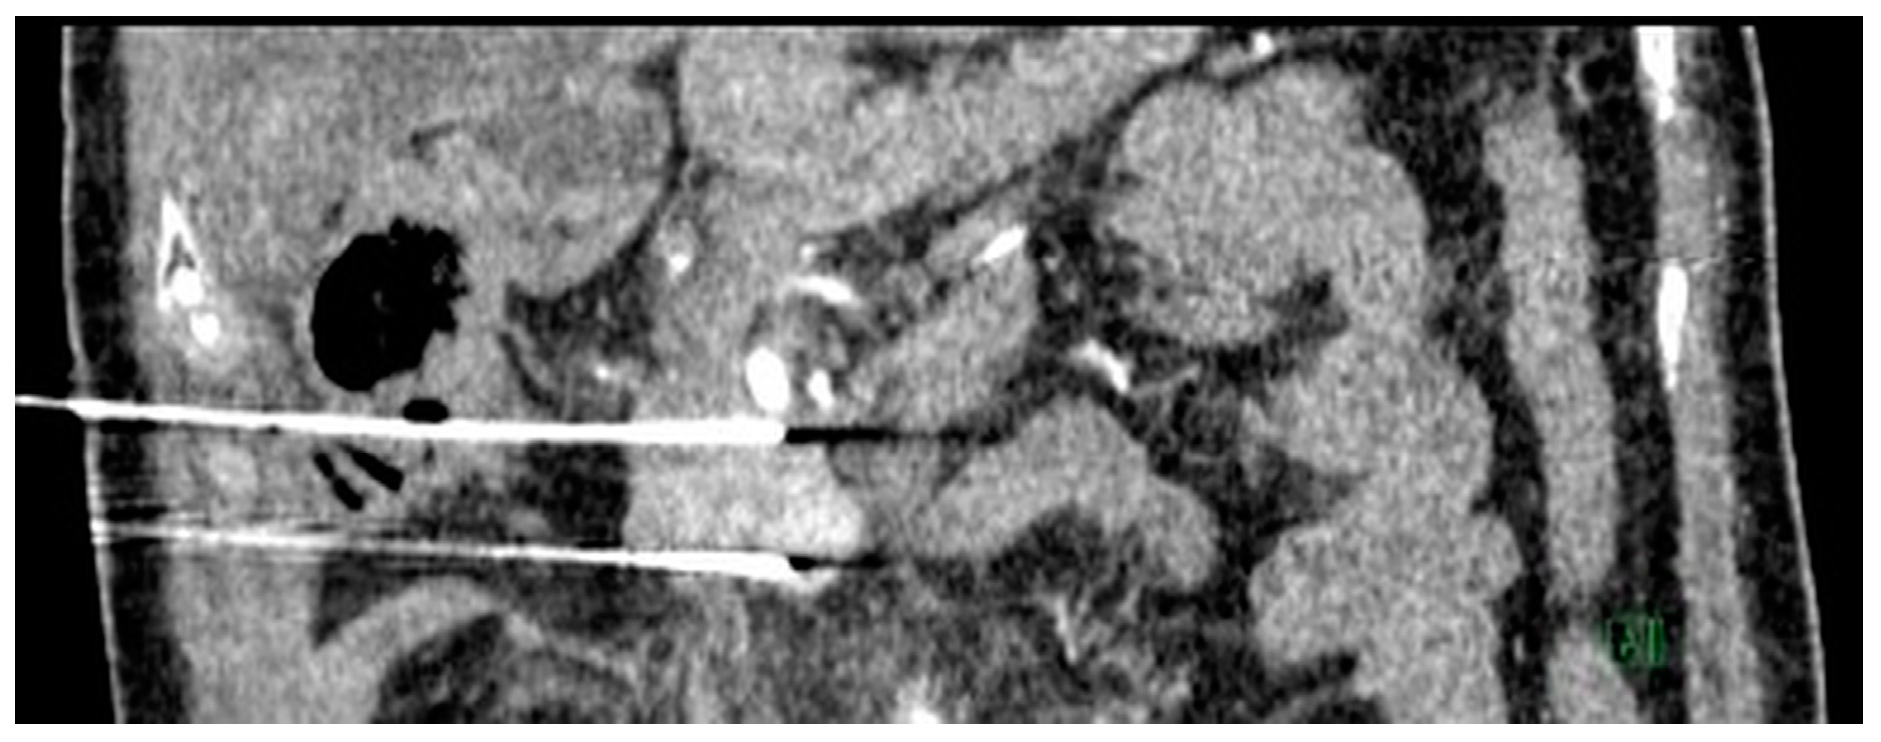

Figure 5.

Intra-operative coronal computed tomography (CT) image demonstrating two irreversible electroporation (IRE) probes inserted in the cranio-caudal orientation into the tumor bed. Percutaneous IRE procedural details: Two IRE probes were inserted in the cranio-caudal orientation into the tumor bed under CT guidance, ensuring the needle is 2 cm apart and parallel—unsheathed 1.5 cm. Two cycles of 90 pulses at 2500 V performed with 12 A rise in current (initial 10 test pulses performed). This was followed by withdrawal of the needles proximally by 1.5 cm with another two cycles of 90 pulses. Post-ablation scan showed no active bleed and air locules seen around the surgical bed secondary to hydrolysis. Needles were then removed.